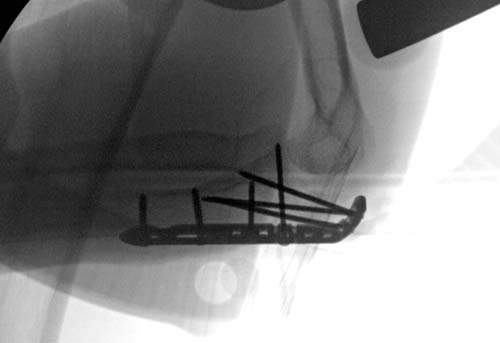

Re: Остеосинтез локтевого отростка - оцените

С фиксацией получилось не так, как задумано. Слабая техника и отсутствие оснащении и так далее... Большинство коллеги едины во мнении и высказались за то, чтобы переделать операцию. Но без клинических данных, которыми владеет “профессор” я бы посоветовал не спешить с заключением. Не все переломы локтевого отростка, даже после неудачной операции, заканчиваются потерей функции.

Здесь примеры, разные по возрасту случаи: В первом, 84-летняя проперирована в другом месте каннюлированным шурупом, потом наблюдалась у нас. Обнаружена несостоятельность винта, но с сохранением движений в суставе. Винт удалили, и от реконструкционной операции отказались... Второй случай у молодого 23 лет, пропущенный перелом локтевого отростка. Обнаружен через 6 недель. Из-за припухлости сделали рентген, движение в полном обьеме. Молодой, не стали рисковать, оперирован...

По поводу техники фиксации. Каждый вид перелома требует своего подхода, и с выходом пластин для локтевого отростка (более10 лет) метод Вебера не является “золотым стандартом”. В дизайне специальных пластин некоторые компании пошли уже по второму кругу. Еще характер перелома тоже изменился и сегодня редко встречаются только поперечные переломы локтевого отростка!